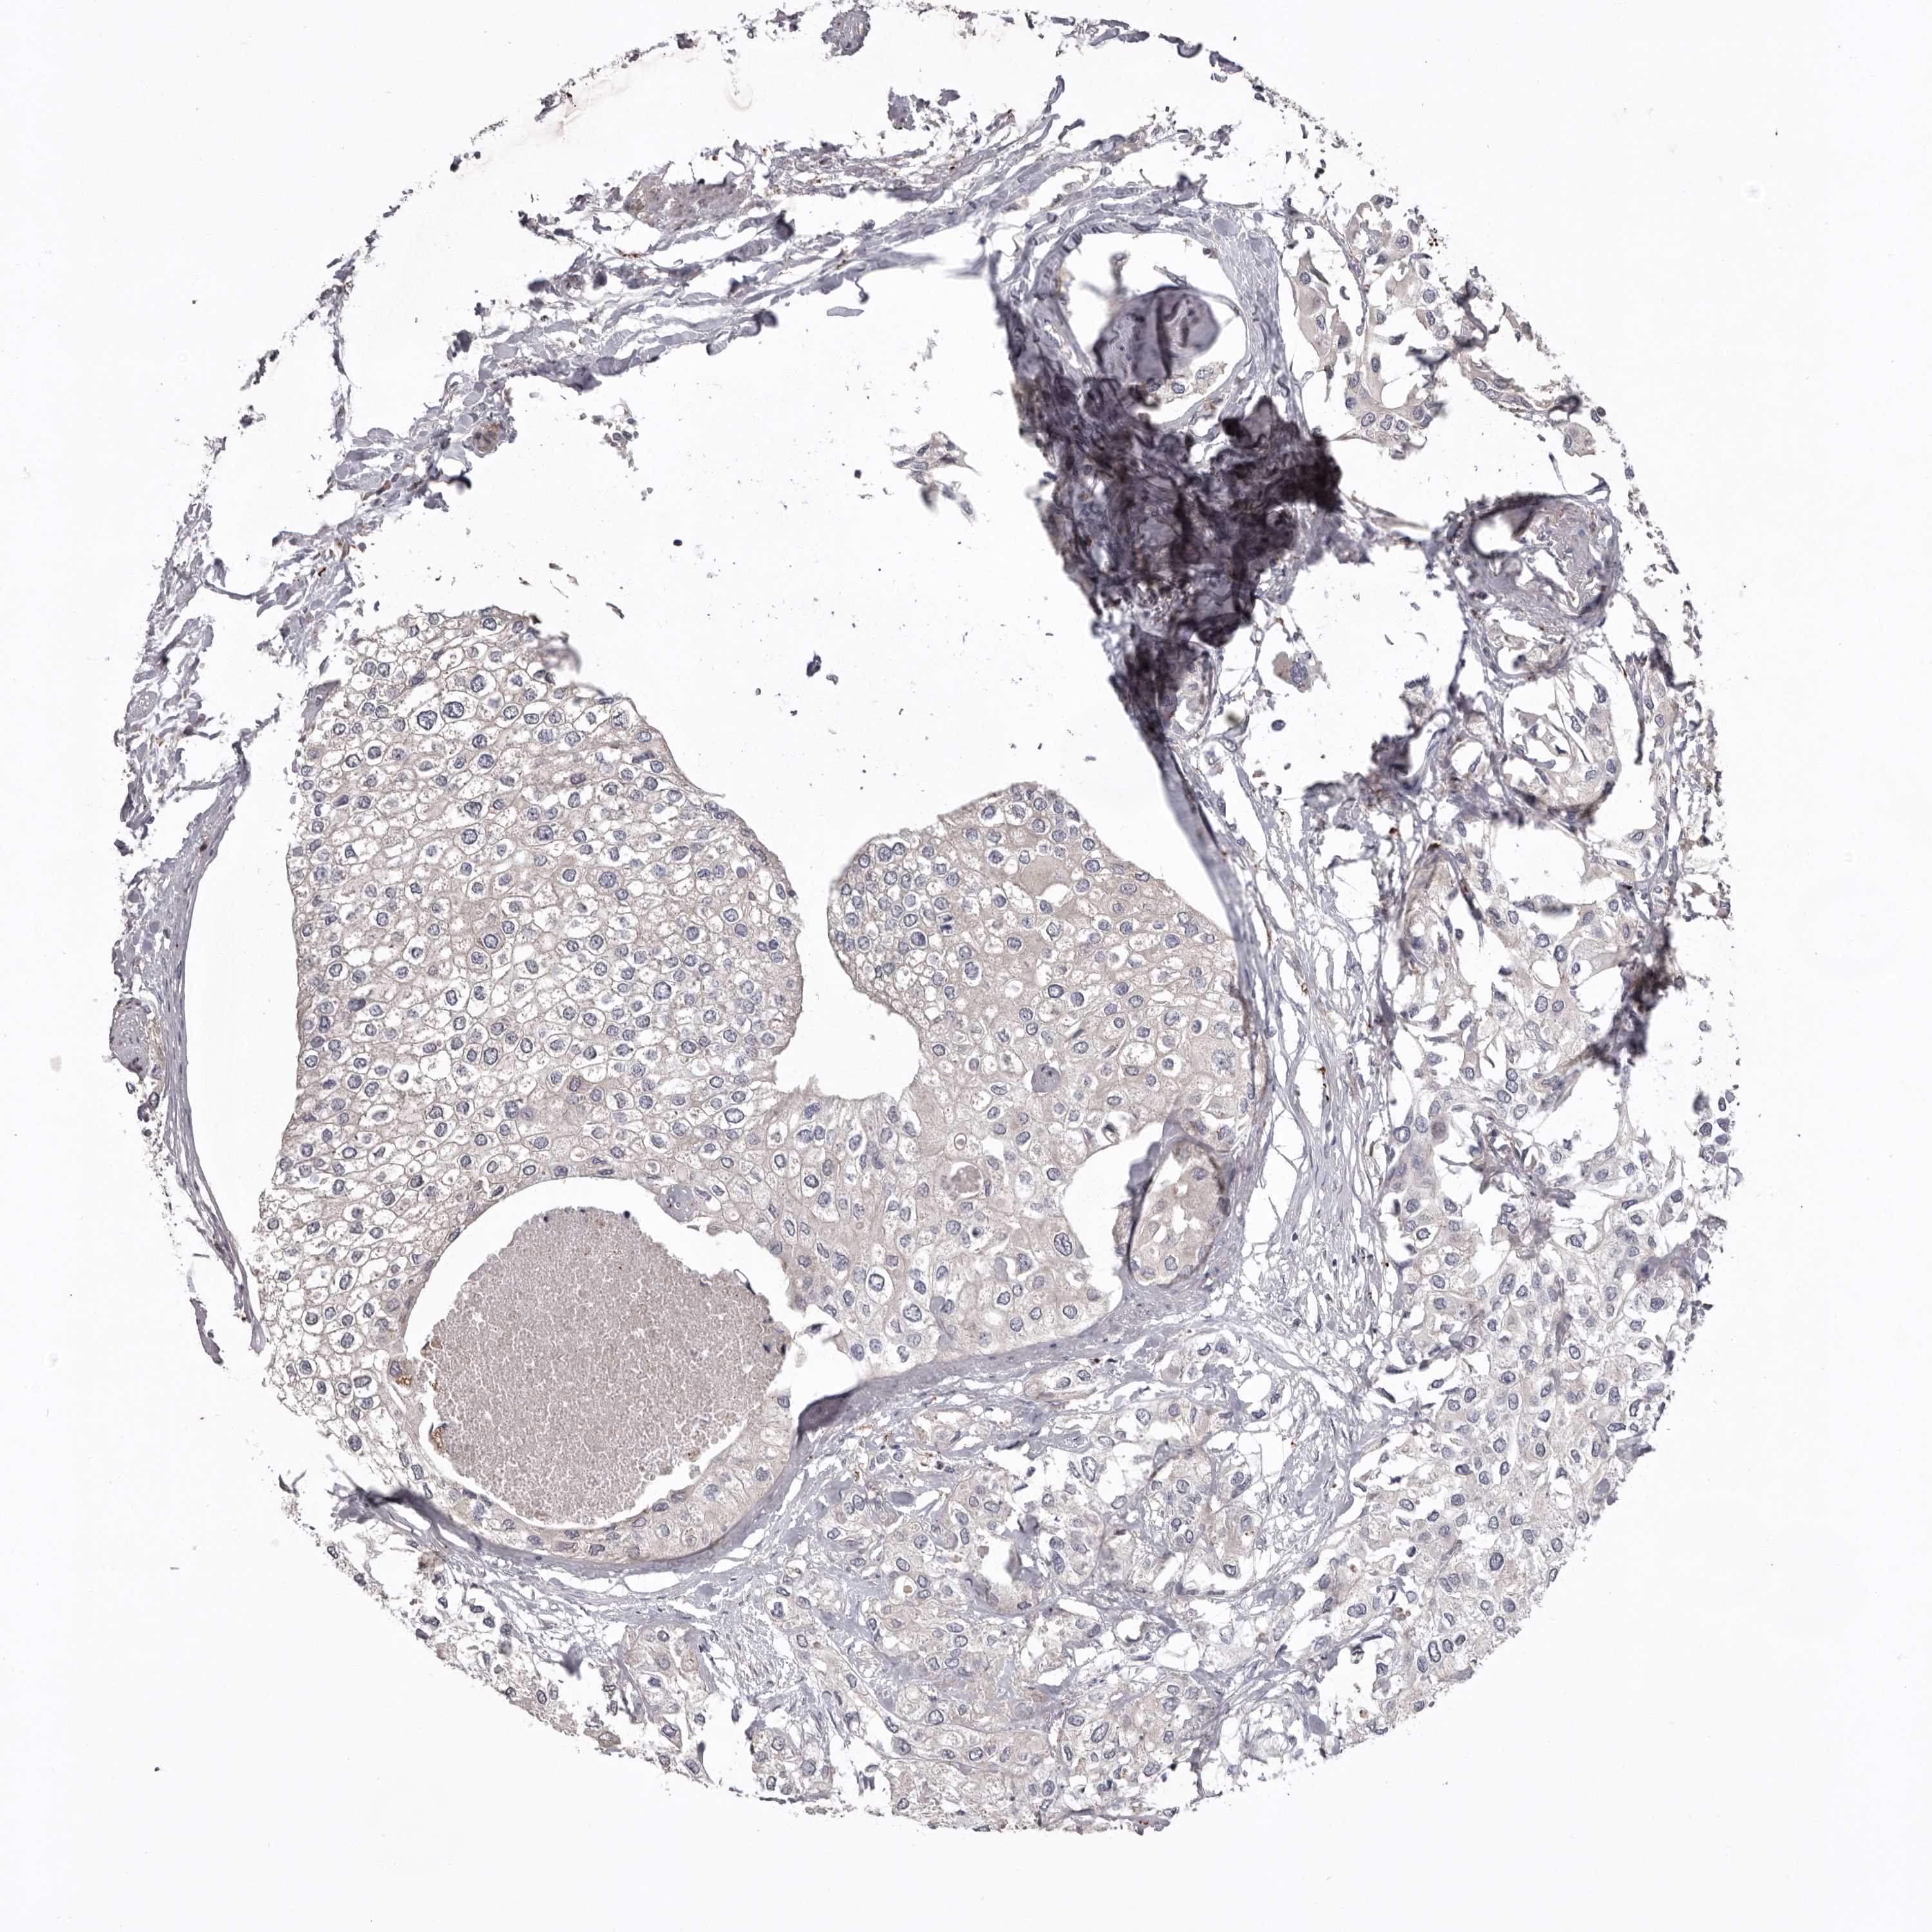

UROTHELIAL CANCER - Protein expressioni

A mouse-over function shows sample information and annotation data. Click on an image to view it in a full screen mode. Samples can be filtered based on level of antibody staining by selecting one or several of the following categories: high, medium, low and not detected. The assay and annotation is described here.

Antibody stainingi

Antibody staining in the annotated cell types in the current human tissue is reported as not detected, low, medium, or high, based on conventional immunohistochemistry profiling in selected tissues. This score is based on the combination of the staining intensity and fraction of stained cells.

Each image is clickable and will lead to virtual microscopy that enables deeper exploration of all samples and also displays staining intensity scores, fraction scores and subcellular localization as well as patient and tissue information for each sample.

Antibody HPA027287

Antibody HPA027289

Urothelial carcinoma, Low grade

Urothelial carcinoma, High grade